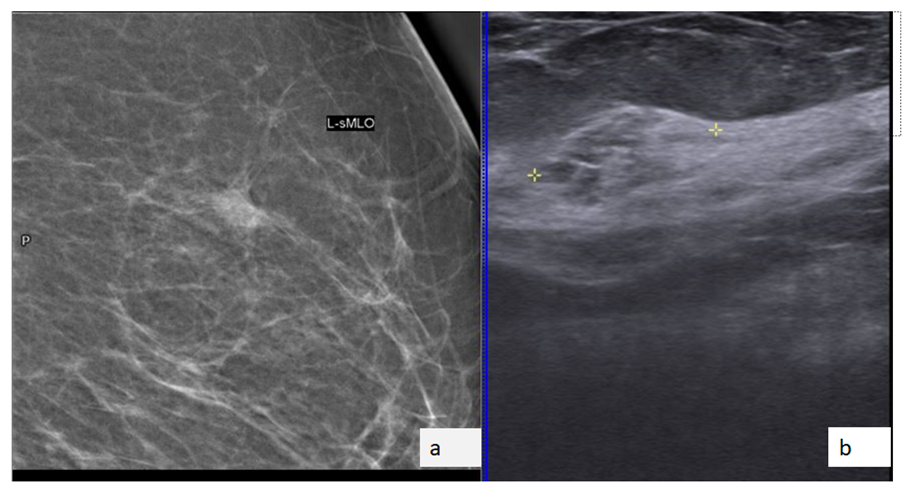

Figure 1: MLO view of left breast of year 2017 (figure 1a ) and 2019 (figure 1b) reveals a new focal asymmetry in upper half of the left breast (white arrow). Figure 2 – (a) The spot compression MLO view shows persistence of asymmetry on spot compression view. (b) Ultrasound reveals a small heterogeneous mass with mixed hyperechoic and hypoechoic areas in the region of mammographic focal asymmetry. Figure 3: (a, b)The mass detected on ultrasound is confirmed to be a true correlate of the mammographic abnormality by injecting a small amount of contrast under ultrasound guidance and a subsequent mammogram is taken. Ultrasound guided biopsy was performed due to increased suspicion of malignancy as the focal asymmetry was an interval appearance in a postmenopausal woman who has previously been treated for contralateral breast cancer, irregular margins of the focal asymmetry on the spot compression view and the presence of mixed hyperechoic and hypoechoic components on ultrasound. Final histopathology - DCIS.